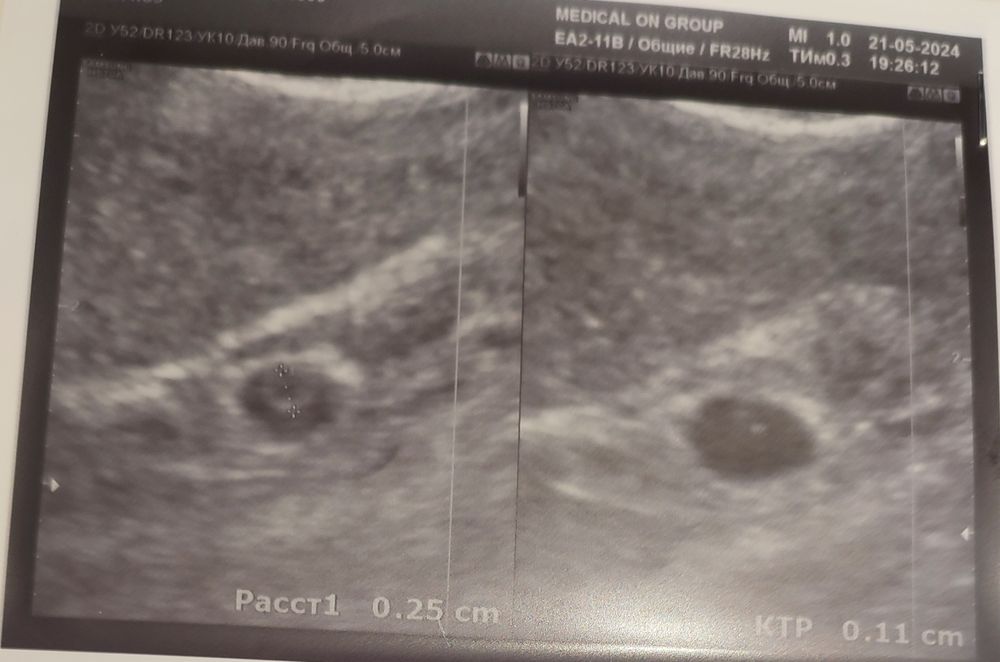

Нашелся эмбрион! Ктр 1.1.

Но...плодное яйцо выросло незначительно: 5,5/5,7 в вскр,

И 6.3 сегодня.

Желточный мешочек вроде подрос ещё, 2,5 мм.